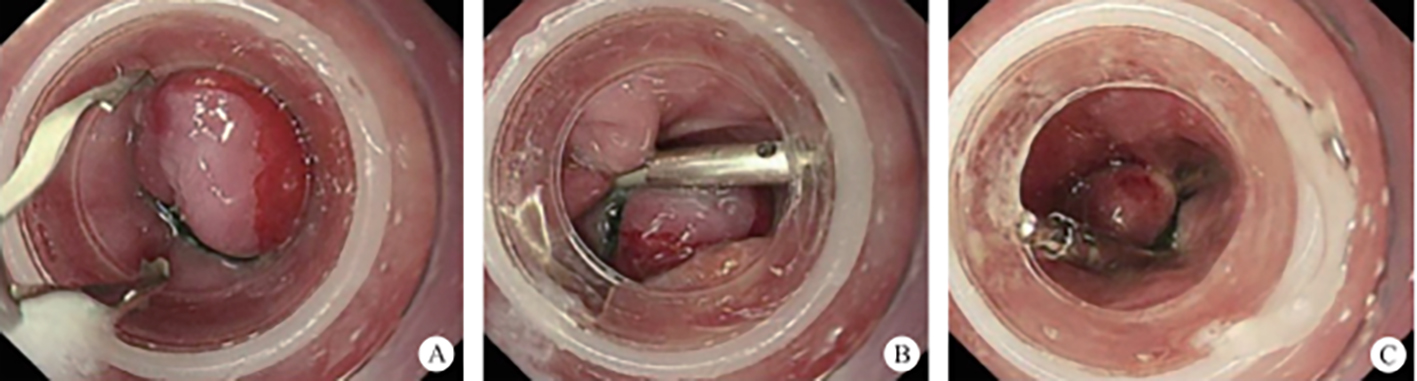

This refers to surgeries that enter the human’s naturally opening orifice and are performed in a natural cavity conforming to super minimally invasive requirements. For instance, through human natural channels such as the nasal cavity, the auditory meatus, the respiratory tract, the mouth, the anus, the vagina, the urinary tract, etc. Let’s take the example of single-channel SMIS surgery of the digestive tract (figure 2.1).

FIG. 2.1 — SMIS through a natural channel.

1. Classic digestive tube channel. The classic digestive tube approach refers to the path through the continuous tube from the mouth to the anus. The wall of the tube is generally divided into the mucosal layer, submucosal layer, muscularis propria layer and serous layer, from the intracavitary to the extracavitary layer. So far, most gastrointestinal endoscopy operations have carried out in this tube.

After endoscopic resection of circumferential esophageal lesions, almost 100% of patients experienced symptoms like esophageal stenosis and an inability to eat. Our team is the first in the world to carry out endoscopic autologous skin flap transplantation to prevent stenosis after endoscopic resection of esophageal circumferential lesions (figure 2.1), and 19 cases of autologous transplantation of skin flaps and simple placement of an esophageal stent for the prevention of esophageal stenosis were compared. The results showed that rate of stent removal for the group who had received an autologous skin flap transplantation was significantly reduced compared to the group with a simple esophageal stent (36.8%–78.9%). Currently, this research is also aimed at optimizing surgical and transplant methods, so as to improve the survival rate of skin flaps and to reduce the rate of occurrence of esophageal stenosis.